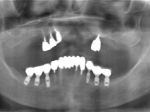

術前レントゲン

術後レントゲン